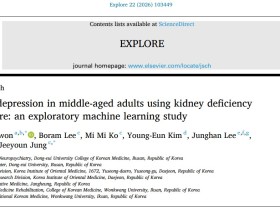

동의대-한의학연, '신허(腎虛)' 기반 중년 우울증 예측 AI 모델 개발[한의신문] 우울증 위험을 예측하는 과정에 한의학의 전통 병리 개념인 ‘신허(腎虛)’를 접목한 인공지능(AI) 기반 예측 모델이 제시돼 주목된다. 특히 중년층 정신건강 관리 분야에서 한의학적 변증 지표의 활용 가능성을 데이터 기반으로 확인했다는 점에서 의미를 더하고 있다. 동의대학교 한의과대학 권찬영 교수와 한국한의학연구원 정지연 박사 연구팀은 한의학의 신허(腎虛) 평가 지표를 활용해 50~65세 중년 성인의 우울증 위험을 예측하는 머신러닝 기반 모델을 개발하고 그 유효성을 검증했다고 밝혔다. 우울증은 생물학적·심리적·사회적 요인이 복합적으로 작용하는 대표적 정신건강 질환으로, 특히 중년 및 노년층에서는 피로감, 수면장애, 식욕 변화, 만성 통증 등 노화 관련 증상과 혼재돼 조기 진단이 쉽지 않은 한계가 있다. 기존 우울증 선별 방식은 주로 자기보고식 심리 평가나 사회환경적 위험요인에 의존해왔으나, 신체 기능 저하와 전신 상태 변화까지 충분히 반영하지 못한다는 지적이 제기돼 왔다. 이에 연구팀은 고령화 코호트(KoMAC)에 참여한 지역사회 거주 중년 성인 1000명의 데이터를 활용해 우울증 예측 모델을 구축했다. 분석 과정에서는 한의학적 병리 개념인 ‘신허’ 상태를 평가하는 신허 설문지(KDQ) 점수를 중심으로 사회적 지지 수준, 체질량지수(BMI) 등 다양한 임상·생활습관 변수를 통합 분석했으며, 머신러닝 알고리즘 간 성능 비교를 통해 최적 모델을 도출했다. 연구 결과, KDQ 총점과 사회적 지지 정도, BMI 등 3가지 핵심 변수만을 조합한 다층 퍼셉트론(MLP) 모델이 가장 우수한 성능을 보였다. 해당 모델은 독립 테스트 데이터셋에서 ROC-AUC 0.820을 기록했으며, 특히 음성 예측도(NPV)가 0.922에 달해 우울증 저위험군을 효과적으로 선별할 수 있는 것으로 나타났다. 이는 지역사회 기반 정신건강 관리에서 1차 스크리닝 도구로 활용 가능성이 높음을 시사한다. 무엇보다 기존의 심리사회적 요인만으로 구성된 예측 모델보다 신허 지표를 추가했을 때 예측 성능이 유의미하게 향상되었다는 점이 주목된다. 연구진은 신허 개념이 단순한 주관적 증상 평가를 넘어, 피로·무기력·수면 이상 등 우울증과 연관된 복합적 신체 취약성을 반영하는 지표로 기능할 수 있다고 분석했다. 이는 전통 한의학의 변증 개념이 데이터 기반 정신건강 예측 모델에서도 설명력을 가질 수 있음을 보여주는 결과라는 설명이다. 또한 이번 연구는 한의학적 진단 개념을 현대 AI 분석기법과 융합해 정량적 예측 모델로 구현했다는 점에서도 의미가 있다는 평가다. 최근 의료계에서는 정신건강 분야에서 설명 가능한 AI(Explainable AI)와 개인 맞춤형 예측 모델 개발 필요성이 커지고 있는 가운데, 전통의학 기반 생체·증후 정보를 디지털 헬스케어 영역에 적용하려는 시도가 확대되고 있다. 연구를 주도한 권찬영 교수는 "이번 연구는 한의학의 신허 개념이 실제 임상에서 우울증의 예측 지표로 활용될 수 있음을 정량적 데이터와 머신러닝을 통해 입증한 첫 번째 사례"라며 "기존의 심리사회적 위험 요인에 신체적 활력 저하를 평가하는 한의학적 지표를 통합함으로써, 중년 성인의 우울증 위험 계층화를 향상시키고 보다 전인적(holistic)인 예방 전략을 수립하는 데 기여할 것으로 기대된다"고 밝혔다. 연구팀은 향후 더 다양한 코호트 및 지역사회 환경에서 모델을 전향적으로 검증하고, 나아가 시상하부-뇌하수체-부신(HPA) 축 지표나 염증 바이오마커 등 객관적인 생리학적 지표를 추가하여 모델을 고도화할 계획이라고 덧붙였다. 이번 연구 성과는 국제 학술지 Explore (SCIE급, IF=2.2) 22권 4호에 게재됐다. (논문명: Predicting depression in middle-aged adults using kidney deficiency questionnaire: an exploratory machine learning study) https://doi.org/10.1016/j.explore.2026.103449

동의대-한의학연, '신허(腎虛)' 기반 중년 우울증 예측 AI 모델 개발[한의신문] 우울증 위험을 예측하는 과정에 한의학의 전통 병리 개념인 ‘신허(腎虛)’를 접목한 인공지능(AI) 기반 예측 모델이 제시돼 주목된다. 특히 중년층 정신건강 관리 분야에서 한의학적 변증 지표의 활용 가능성을 데이터 기반으로 확인했다는 점에서 의미를 더하고 있다. 동의대학교 한의과대학 권찬영 교수와 한국한의학연구원 정지연 박사 연구팀은 한의학의 신허(腎虛) 평가 지표를 활용해 50~65세 중년 성인의 우울증 위험을 예측하는 머신러닝 기반 모델을 개발하고 그 유효성을 검증했다고 밝혔다. 우울증은 생물학적·심리적·사회적 요인이 복합적으로 작용하는 대표적 정신건강 질환으로, 특히 중년 및 노년층에서는 피로감, 수면장애, 식욕 변화, 만성 통증 등 노화 관련 증상과 혼재돼 조기 진단이 쉽지 않은 한계가 있다. 기존 우울증 선별 방식은 주로 자기보고식 심리 평가나 사회환경적 위험요인에 의존해왔으나, 신체 기능 저하와 전신 상태 변화까지 충분히 반영하지 못한다는 지적이 제기돼 왔다. 이에 연구팀은 고령화 코호트(KoMAC)에 참여한 지역사회 거주 중년 성인 1000명의 데이터를 활용해 우울증 예측 모델을 구축했다. 분석 과정에서는 한의학적 병리 개념인 ‘신허’ 상태를 평가하는 신허 설문지(KDQ) 점수를 중심으로 사회적 지지 수준, 체질량지수(BMI) 등 다양한 임상·생활습관 변수를 통합 분석했으며, 머신러닝 알고리즘 간 성능 비교를 통해 최적 모델을 도출했다. 연구 결과, KDQ 총점과 사회적 지지 정도, BMI 등 3가지 핵심 변수만을 조합한 다층 퍼셉트론(MLP) 모델이 가장 우수한 성능을 보였다. 해당 모델은 독립 테스트 데이터셋에서 ROC-AUC 0.820을 기록했으며, 특히 음성 예측도(NPV)가 0.922에 달해 우울증 저위험군을 효과적으로 선별할 수 있는 것으로 나타났다. 이는 지역사회 기반 정신건강 관리에서 1차 스크리닝 도구로 활용 가능성이 높음을 시사한다. 무엇보다 기존의 심리사회적 요인만으로 구성된 예측 모델보다 신허 지표를 추가했을 때 예측 성능이 유의미하게 향상되었다는 점이 주목된다. 연구진은 신허 개념이 단순한 주관적 증상 평가를 넘어, 피로·무기력·수면 이상 등 우울증과 연관된 복합적 신체 취약성을 반영하는 지표로 기능할 수 있다고 분석했다. 이는 전통 한의학의 변증 개념이 데이터 기반 정신건강 예측 모델에서도 설명력을 가질 수 있음을 보여주는 결과라는 설명이다. 또한 이번 연구는 한의학적 진단 개념을 현대 AI 분석기법과 융합해 정량적 예측 모델로 구현했다는 점에서도 의미가 있다는 평가다. 최근 의료계에서는 정신건강 분야에서 설명 가능한 AI(Explainable AI)와 개인 맞춤형 예측 모델 개발 필요성이 커지고 있는 가운데, 전통의학 기반 생체·증후 정보를 디지털 헬스케어 영역에 적용하려는 시도가 확대되고 있다. 연구를 주도한 권찬영 교수는 "이번 연구는 한의학의 신허 개념이 실제 임상에서 우울증의 예측 지표로 활용될 수 있음을 정량적 데이터와 머신러닝을 통해 입증한 첫 번째 사례"라며 "기존의 심리사회적 위험 요인에 신체적 활력 저하를 평가하는 한의학적 지표를 통합함으로써, 중년 성인의 우울증 위험 계층화를 향상시키고 보다 전인적(holistic)인 예방 전략을 수립하는 데 기여할 것으로 기대된다"고 밝혔다. 연구팀은 향후 더 다양한 코호트 및 지역사회 환경에서 모델을 전향적으로 검증하고, 나아가 시상하부-뇌하수체-부신(HPA) 축 지표나 염증 바이오마커 등 객관적인 생리학적 지표를 추가하여 모델을 고도화할 계획이라고 덧붙였다. 이번 연구 성과는 국제 학술지 Explore (SCIE급, IF=2.2) 22권 4호에 게재됐다. (논문명: Predicting depression in middle-aged adults using kidney deficiency questionnaire: an exploratory machine learning study) https://doi.org/10.1016/j.explore.2026.103449 -